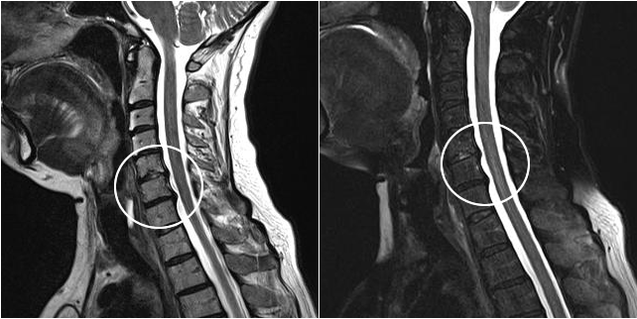

Modern diagnostic methods include MRI and CT, which make it possible to most accurately study the processes of destruction of cartilage and bone tissue.In addition, with this technique it is convenient to diagnose hernias and other soft tissue defects close to the source of the disease.